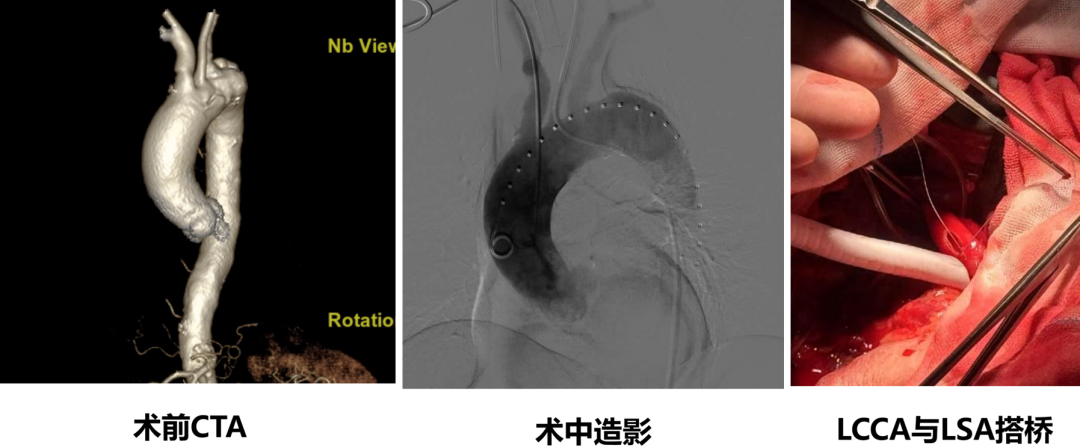

★ Case2:胸主动脉瘤,带分支支架重建LCCA+原位开窗技术重建LSA

★ Case3:B型主动脉夹层,带分支支架重建LCCA+体外开窗技术重建LSA